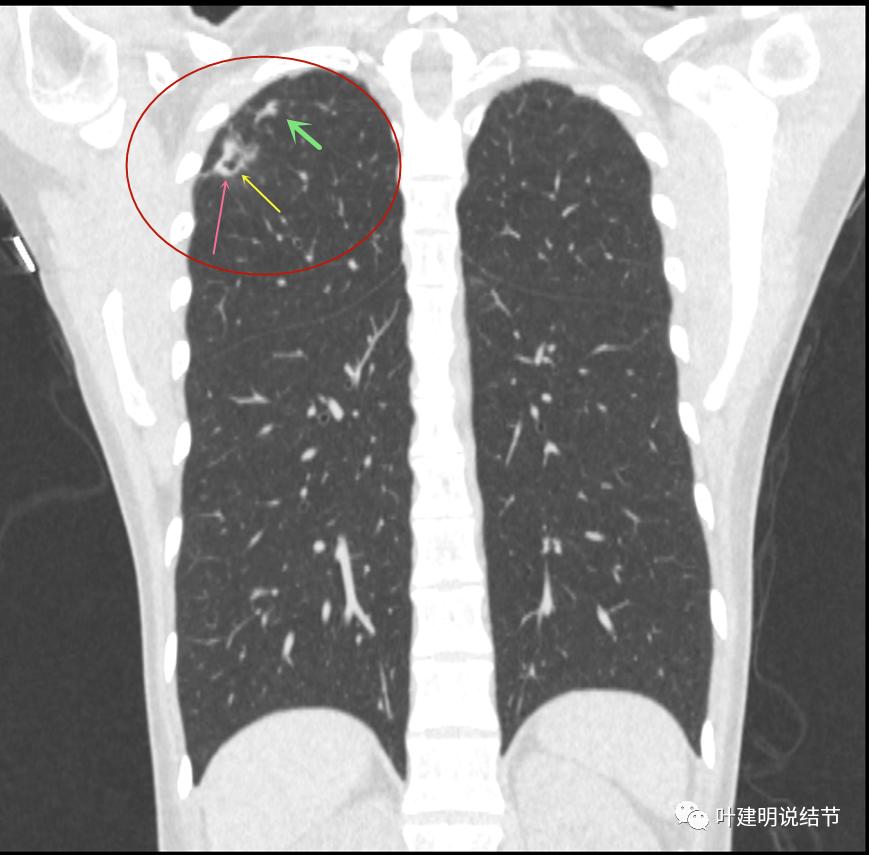

我们再来瞧瞧冠状位与矢状位的图像:

病灶较散,有磨玻璃影,但磨玻璃的边缘模糊不清(砖色箭头),囊壁密度过高(粉色箭头),毛刺样的结构偏长,空洞内壁较光滑,有卫星灶(绿色箭头)

病灶邻近胸膜增厚明显(蓝色箭头);病灶似三角形,边缘平直(桔色箭头);有磨玻璃淡且散,边缘不清(砖色箭头);有卫星病灶(绿色箭头)